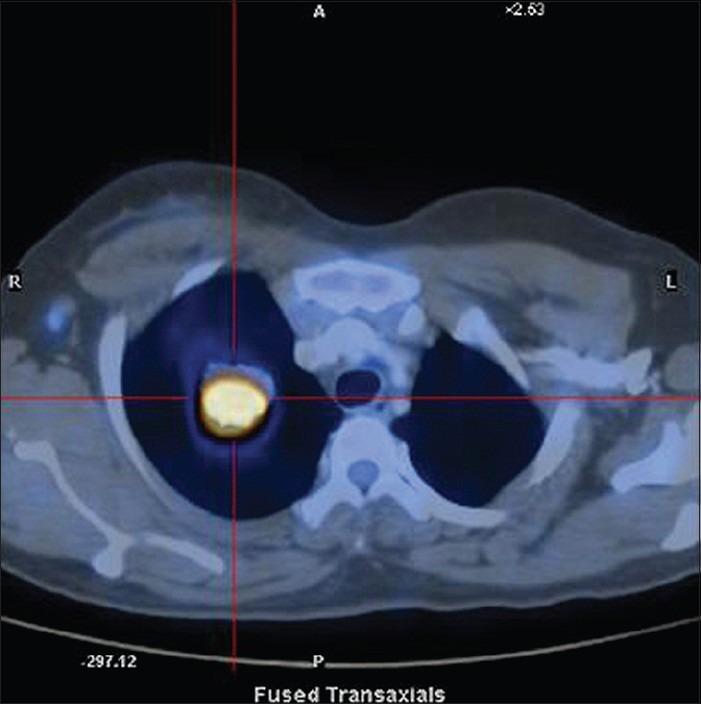

Inflammatory myofibroblastic tumor (IMT) is a rare neoplasm, most commonly seen in children and adolescents. It can occur in nearly every part of the body. Imaging properties and the clinical presentation of IMT can mimic malignant process. A 41-year-old female presented with cough of 3 months duration. Chest X-ray showed a coin shadow in the right upper lobe. Positron emission tomography/computed tomography scan showed a 3.2 × 2.4 cm lesion with homogeneous appearance with a very high fluorodeoxyglucose uptake value, suggesting a neoplastic process. She underwent lobectomy and the final diagnosis was IMT.

炎性肌纤维母细胞瘤(IMT)是一种罕见的肿瘤,最常见于儿童和青少年。它几乎可发生于身体的各个部位。IMT的影像学特征和临床表现可类似于恶性病变。一名41岁女性因持续3个月的咳嗽就诊。胸部X线显示右上叶有一个硬币状阴影。正电子发射断层扫描/计算机断层扫描显示一个3.2×2.4厘米的病灶,外观均匀,氟脱氧葡萄糖摄取值非常高,提示为肿瘤性病变。她接受了肺叶切除术,最终诊断为IMT。